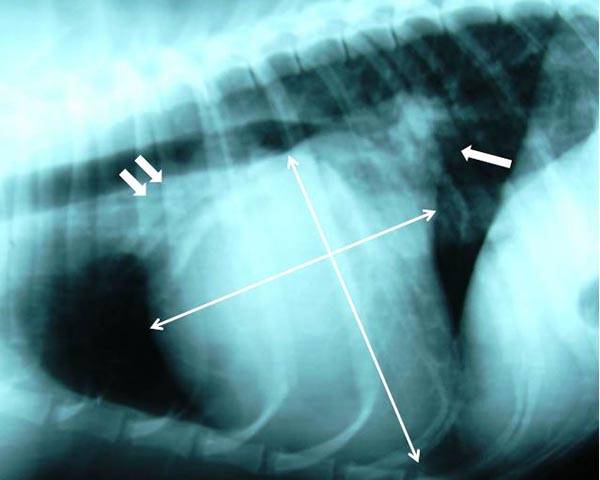

Right lateral thoracic radiograph showing measurement of the Vertebral Heart Sum (or Vertebral Heart Score/Size, VHS).

• Vertebral heart sum (VHS) >10.5